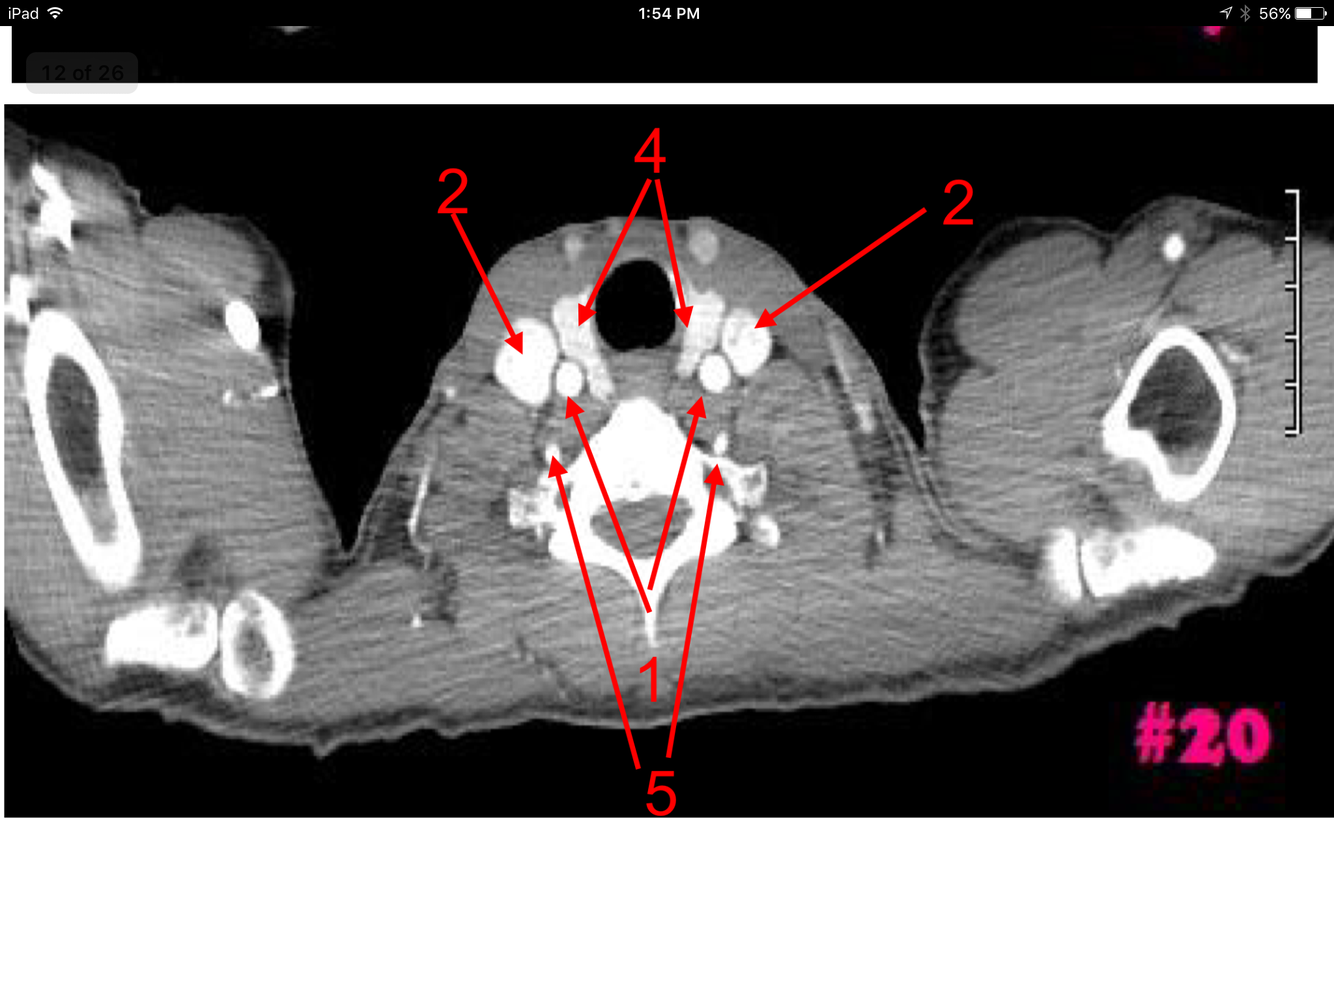

12

A

Superior vena cava

Ascending aorta

Descending aorta

Trachea